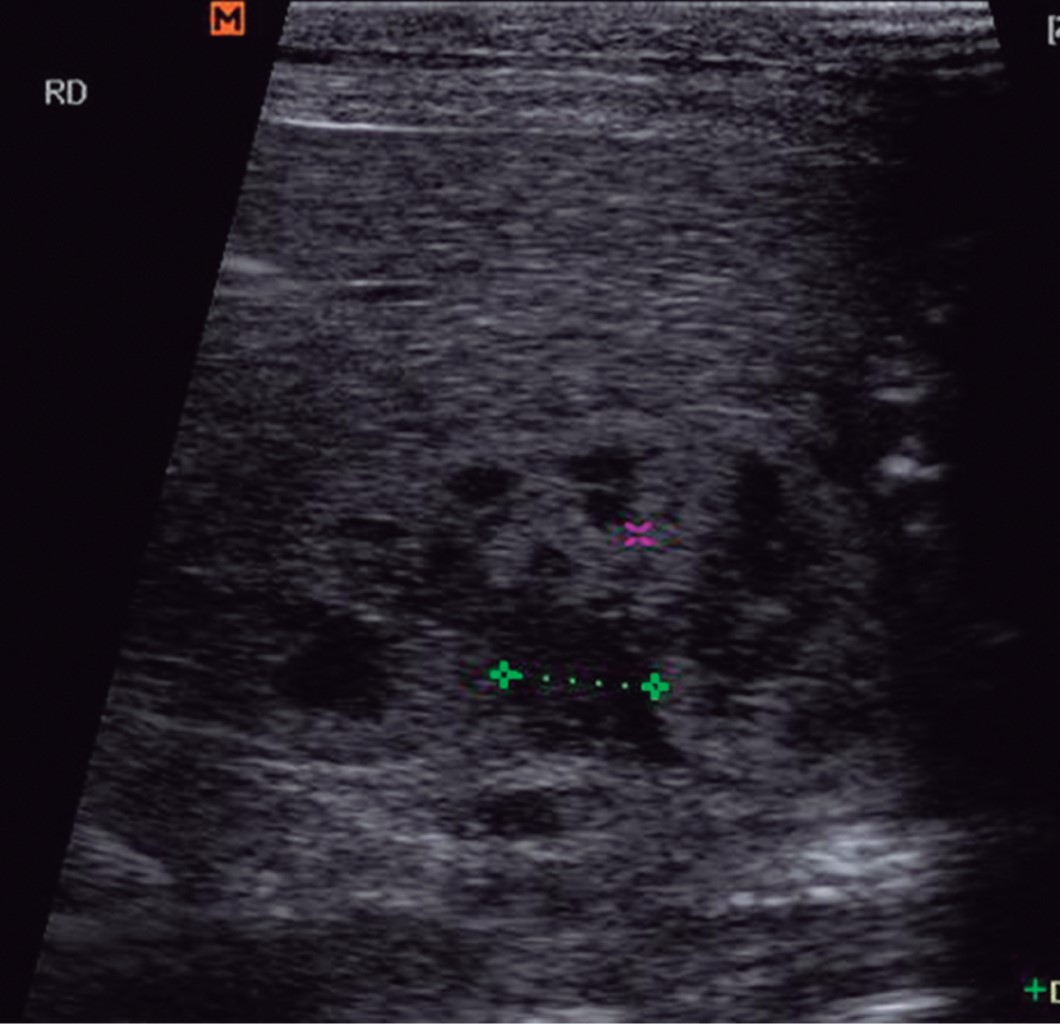

Neonatal renal injury secondary to maternal antihypertensive therapy: a case report

Introduction: the kidney is the organ in charge of homeostasis in extrauterine life. The RAS (renin angiotensin system) has a fundamental role during fetal organogenesis and especially in kidney development. Renal failure can originate within the uterus, prenatal causes include maternal consumption of angiotensin-converting enzyme inhibitors (ACE inhibitors), angiotensin II receptor blockers (ARBs) and can also produce oligohydramnios, fetal growth restriction, among others. others. Case report: this is a newborn whose intrauterine growth restriction and oligohydramnios were detected at birth, who was subsequently admitted to the neonatal intensive care unit due to acute kidney injury. Conclusion: treatment with ARBs during the second and third trimester of pregnancy is associated with serious complications in the neonate from the prenatal period such as oligohydramnios, an hydramnios, renal failure, anuria, to mention a few.

Figure 1